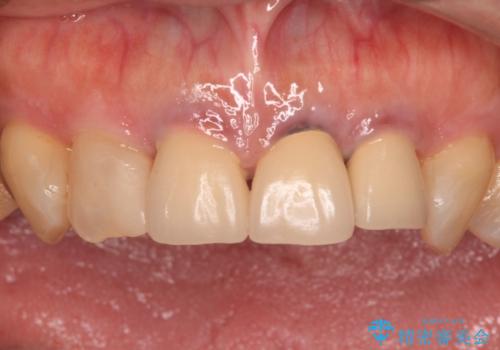

- 黄色みのある前歯のセラミックを、明るい色に替えたいとのことで来院された患者様です。

透明感がないことも気になっていたため、オールセラミッククラウンでは透けてしまう可能性のある金属の土台をファイバーコアに置き換え、1トーン明るいクラウンにて仕上げていくこととしました。

透明感のある自然な色合いとなり、患者様には大変満足していただけました。